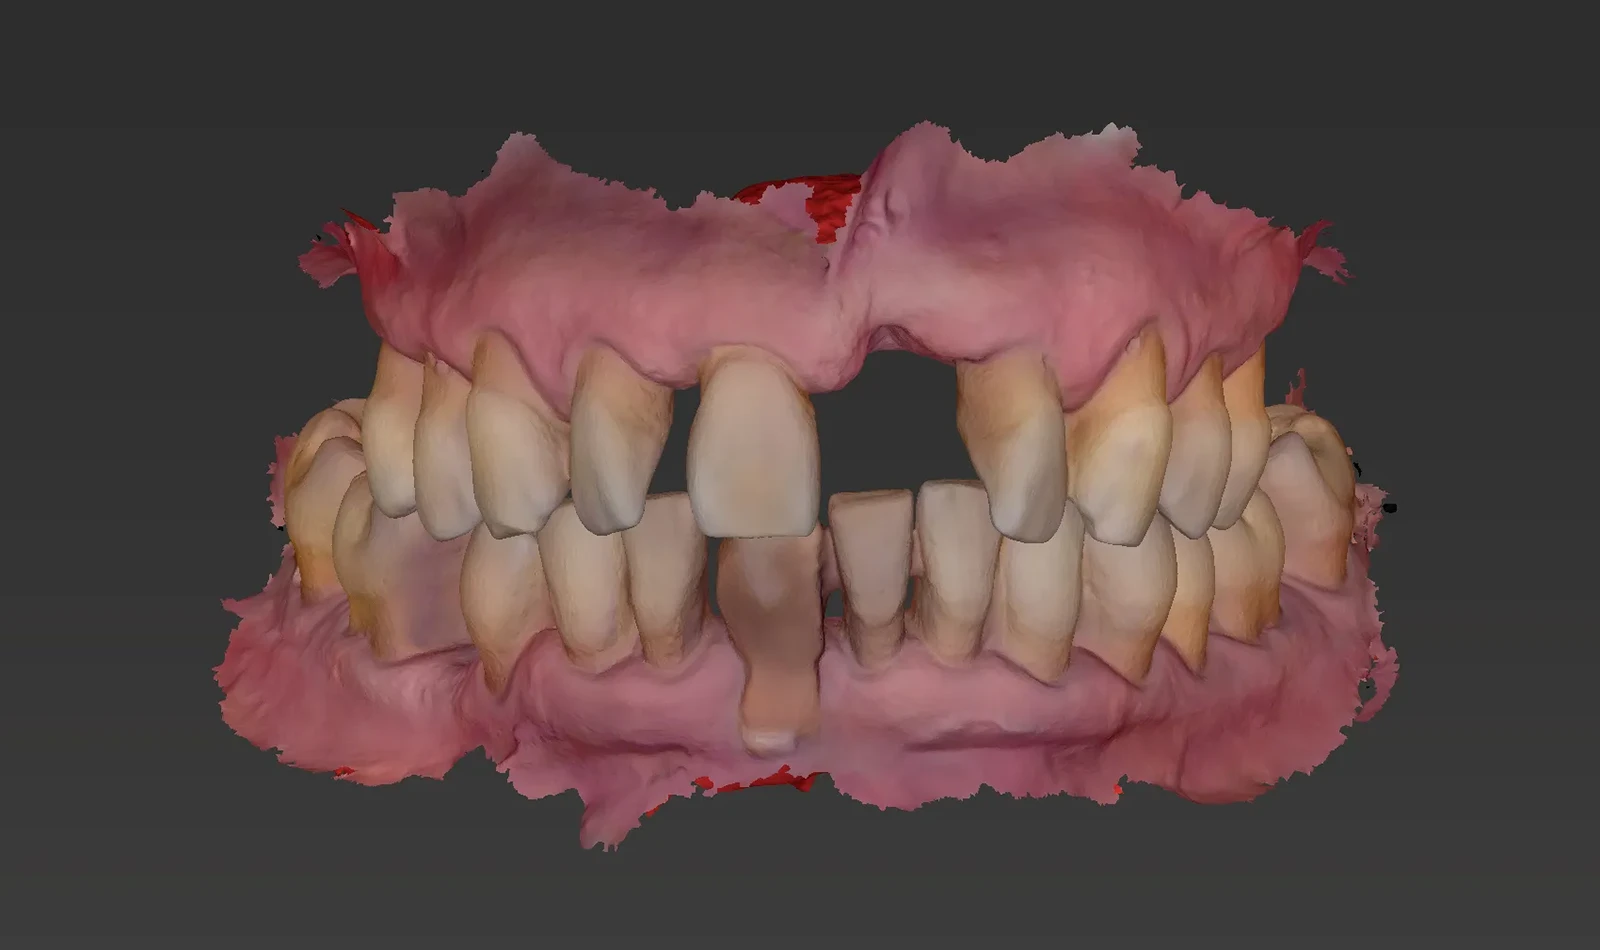

De 61 años nos visita con dientes dañados por caries y una prótesis antigua que ya no podía utilizar. Gracias a la planificación digital y la cirugía guiada, realizamos las extracciones y colocamos implantes con una prótesis fija el mismo día. Recuperó su sonrisa y la confianza de inmediato.